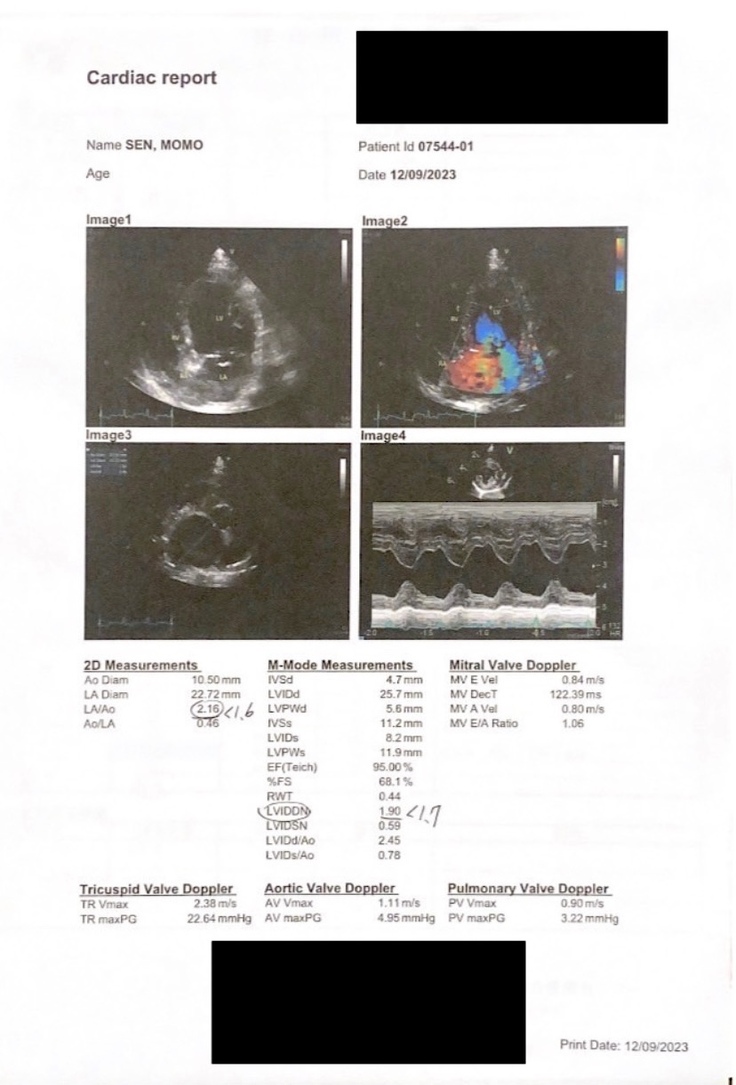

昨年11月、萌萌は僧帽弁閉鎖不全症ステージCと診断され、現在は日々薬を服用し、状態を維持しようと努力していますが、ステージDに悪化し、薬物療法も増え、腎臓に大きな負担をかけており、状況が深刻です。

◀︎心臓が非常に大きくなりました

▼彼の小さな体には、心臓病が最も危険なステージ Dに進行しており、毎日4つの異なる種類の薬を飲まなければなりません。心臓の薬、利尿剤、降圧薬などが含まれ、これらの薬は腎臓に負担をかけ、腎不全のリスクをもたらす可能性があります。

心臓病だと診断されてから10ヶ月経ちましたが、彼の病状はStage Dに進行してしまい、心臓の衰弱や肺水腫の危険性が常にあります。